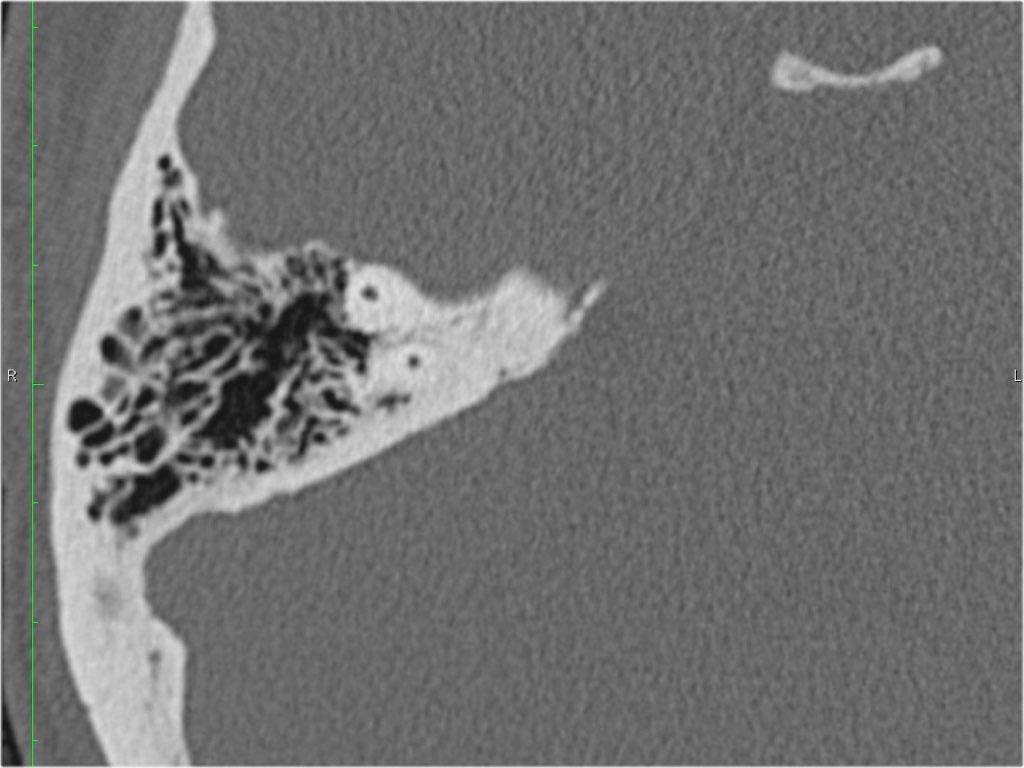

Trong bài tổng quan này, chúng tôi trình bày giải phẫu bình thường trên mặt phẳng cắt ngang (axial) và mặt phẳng cắt đứng ngang (coronal) của xương thái dương thông qua việc duyệt qua các hình ảnh.

Một số cấu trúc được thảo luận chi tiết hơn với trọng tâm là các bệnh lý liên quan.

Giải phẫu xương đá trên mặt phẳng cắt ngang (Axial)

Cuộn qua các hình ảnh.